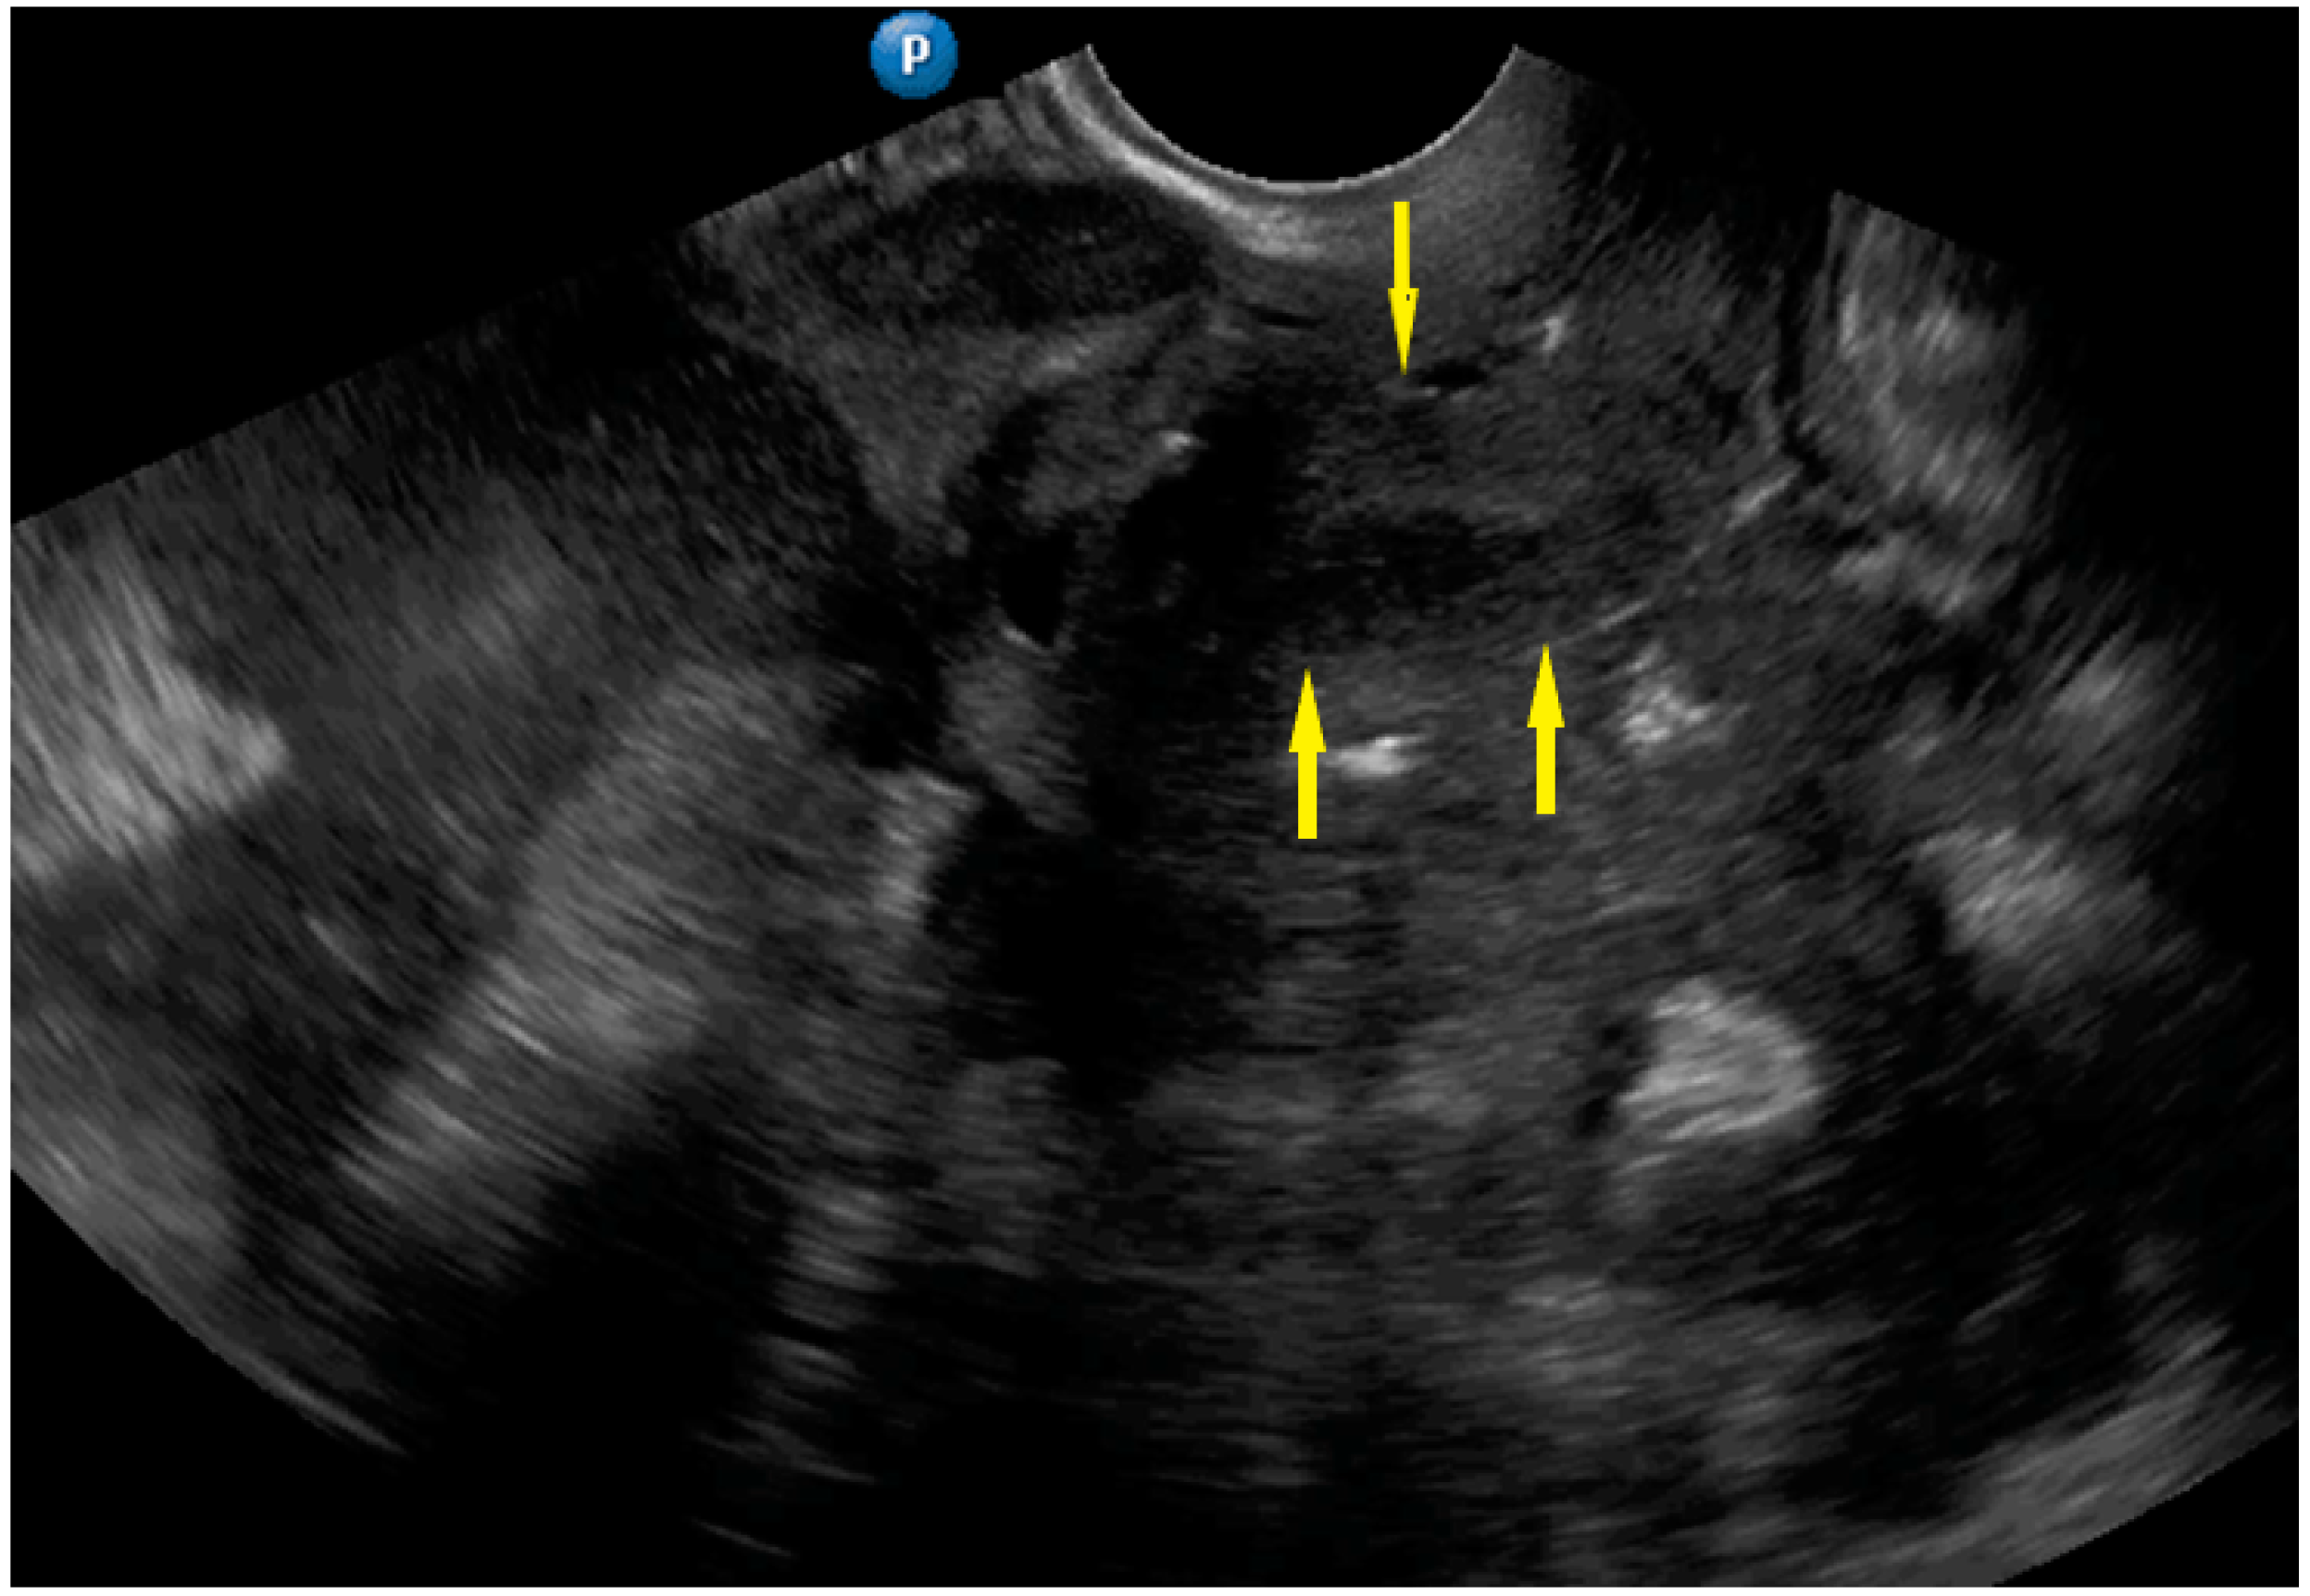

| Frozen pelvis | Massive pelvic involvement: hypoechogenic tissue in the peritoneum in the pouch of Douglas, forming cohesion between ovarian masses, bowel, uterus, and posterior pelvic wall. It manifests in the dynamic ultrasound examination: absence of sliding sign between the rectum and uterus/ovaries and between the uterus, urinary bladder, and pelvic walls. | Figure 12 | Video S12 |